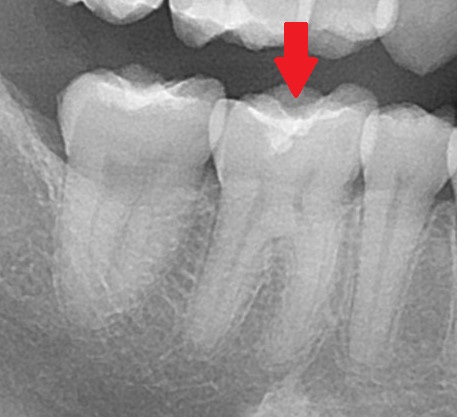

奥歯の虫歯なのですが、どこにあるかわかりますか?

正解は・・・

こちらが全て虫歯です。

よく見れば大きい「C3」の虫歯もありますが、小さい虫歯だらけの状態です。

虫歯は歯と歯の間から虫歯になっているために、患者さん自身では気づいていませんでした。

ここで「C1~C2」とあります。虫歯はが大きくなると判別つきやすいのですが、小さいものは正確に範囲が分からないことが多いです。

ですのでレントゲンからでは、虫歯があるのは分かりますが「C2まで進行しているかなぁ?」と推測することまでしか出来ません。

実際に治療をすると「C2」だったと後で分かります。